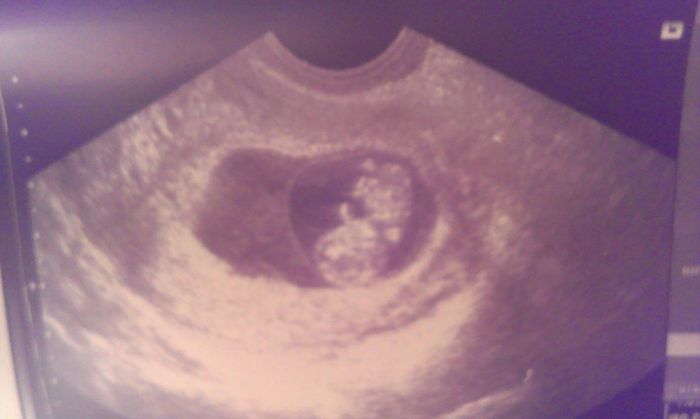

Autor: Hanula   6.2.2015 v 22:12

Tady je nas broucek...

Autor: Hanula   6.2.2015 v 22:14

Akorat jsem to vyfotila opačně;)